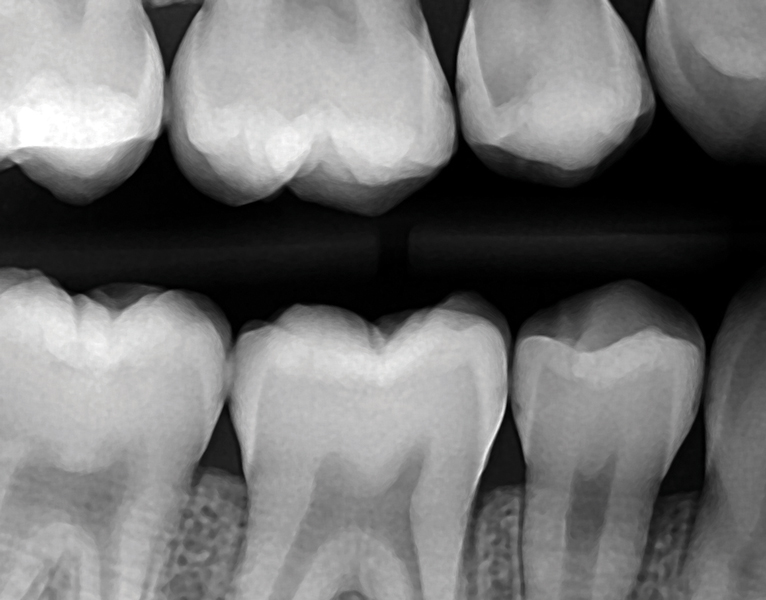

Dental Margin Placement . Should the margin be placed for periodontal health, or aesthetics and an increased risk of periodontal disease? When restoring a tooth with a scc, the clinician may. Frank spear discusses the use of margin placement and cord placement technique when restoring teeth at the gingival margin. The mini case reports presented herein demonstrate why aggressive tooth preparations and subgingival margin placement should be questioned. There is no easy answer, but what is clear is that, to avoid future complaints. A solution or problem to short clinical crown. The first option is to place the margin supragingivally so as not to traumatize the unstable tissue. The second option is to place. This technique allows relocation of subgingival margins to a more favorable supragingival position, overcoming limitations in moisture. Restoration’s margin marks the transition between the restoration itself and the finishing line of the adjacent tooth tissue.